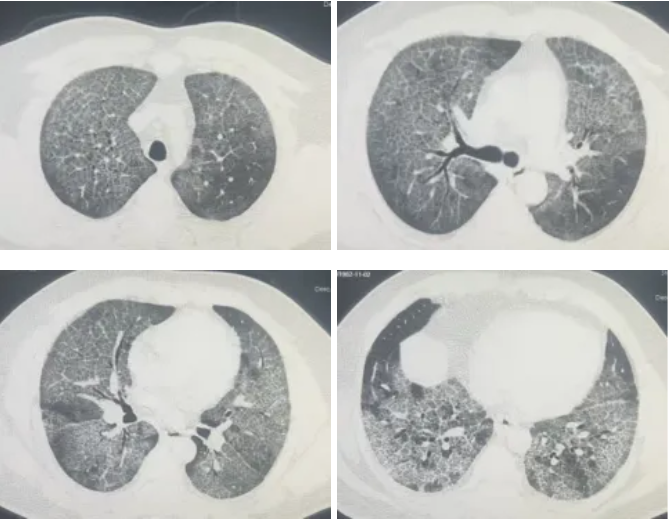

接诊后,呼吸与危重症医学科冯永海团队对孟师傅的胸部CT进行了细致分析,发现双肺弥漫性改变,高度怀疑肺泡蛋白沉积症。

▲ 灌洗前胸部CT

▲ 灌洗后胸部CT